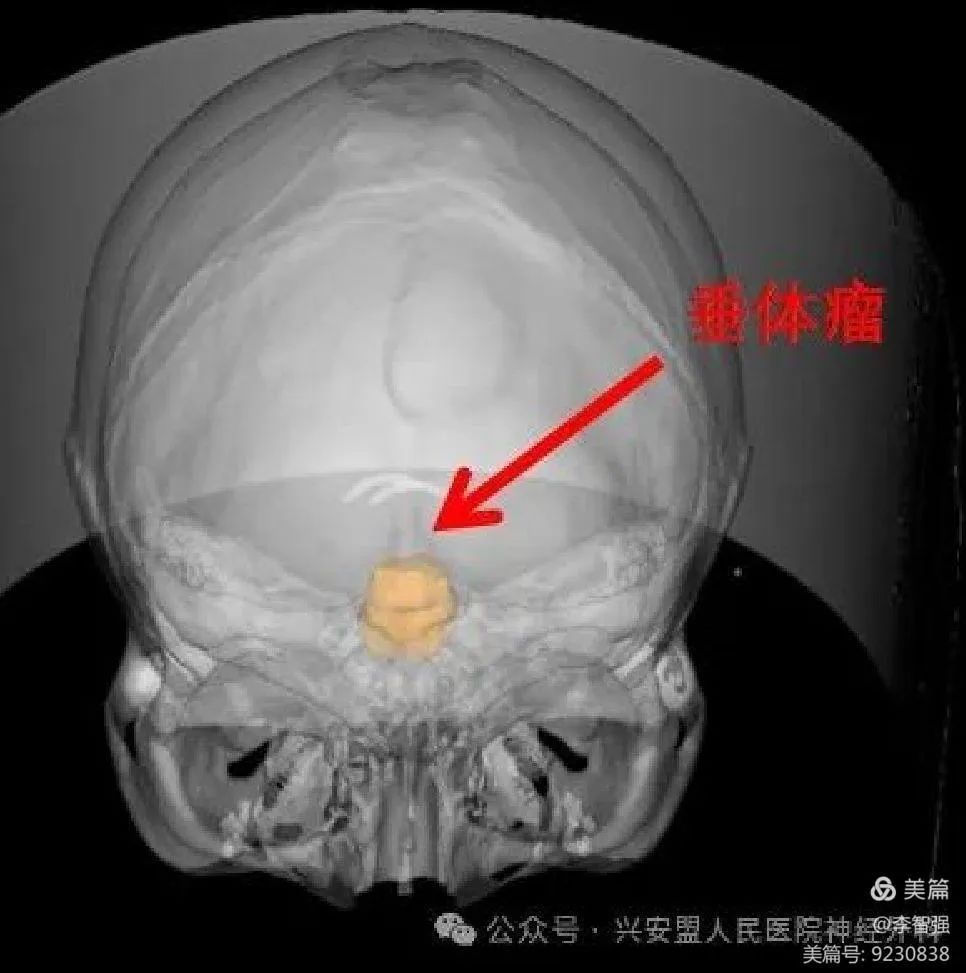

术前将头颅CT与核磁融合后,精准三维重建皮肤、颅骨、瘤体

手术在定位机器人导航下逐步推进,高速磨钻慢慢磨除厚厚的颅底骨质,直至到达硬膜,导航探针定位垂体瘤,快速、精确!